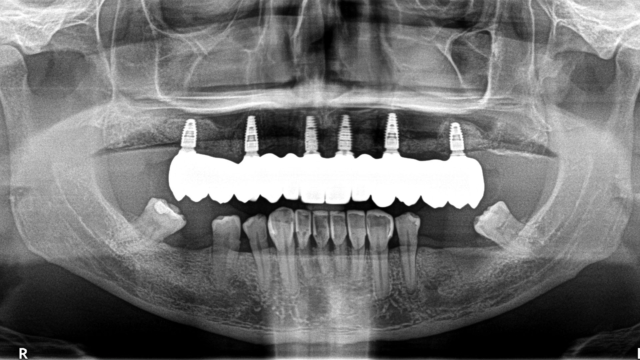

An x-ray of someone's jaw showing their top set of teeth as implants.